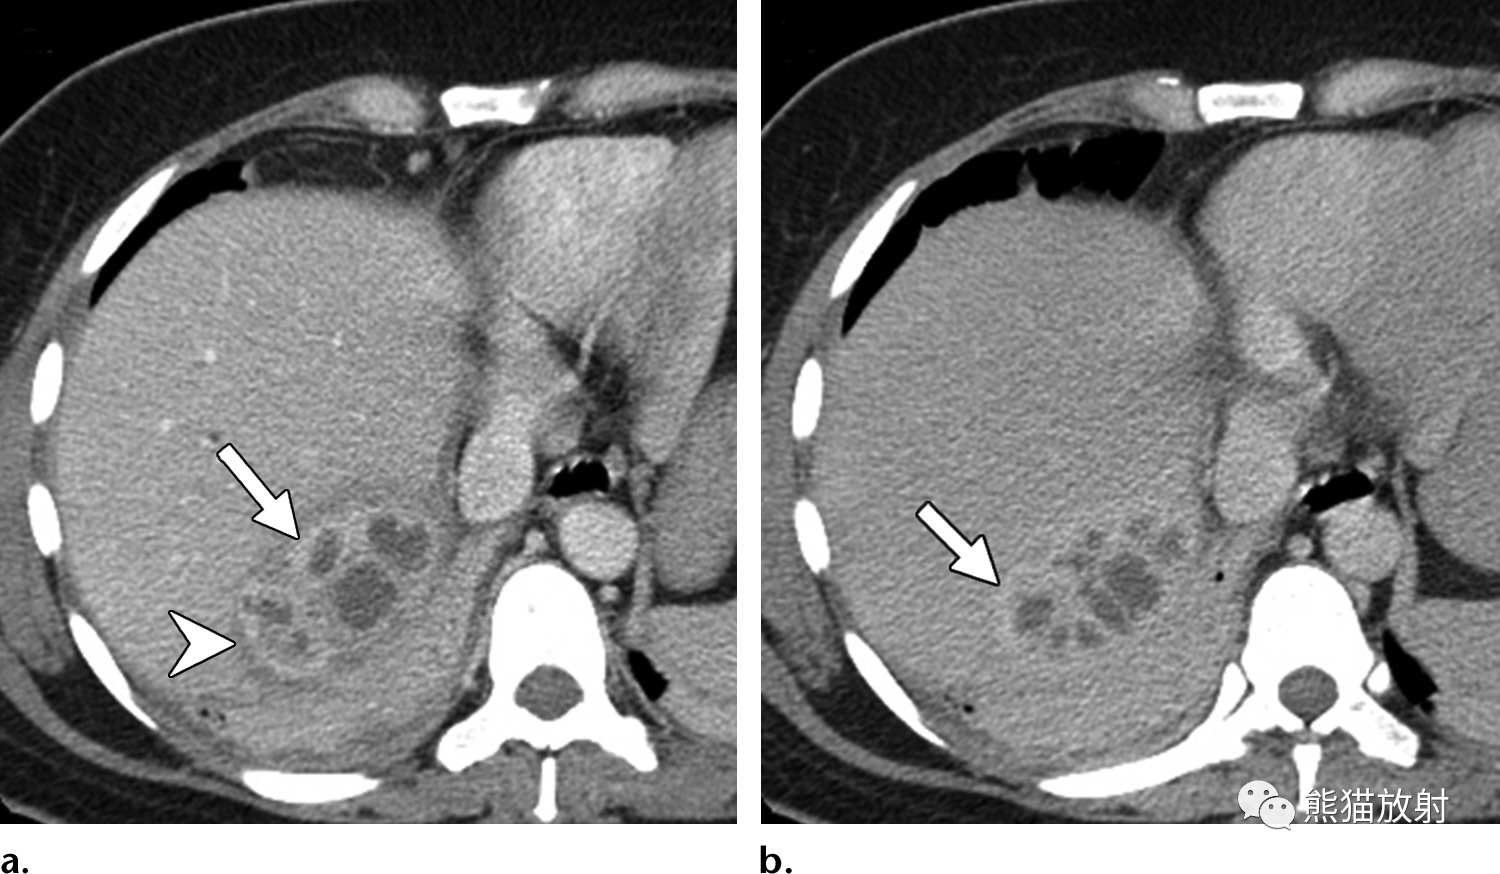

4faf52959f139f7e497ee2e0b5a371f9.png 69岁男性,胆总管结石患者,发热,实性机化性肝脓肿。(a) 动脉早期CT图像显示具有“靶征”表现的结节,中心早期强化,与肝实质相似,边缘密度较低。(b) 延迟期病灶中心呈等密度,外周环状强化(箭头)。由于脓液吸收而无中心液体内容物,使脓肿呈实性外观,可能难以与肝内胆管细胞癌相鉴别。